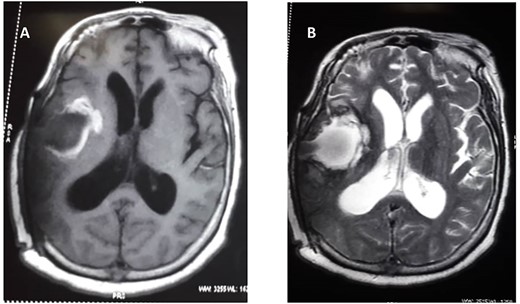

She subsequently had right frontotemporal craniotomy and tumour excision. Intraoperative findings were those of a mixed consistency mass, which was firm, gritty with areas of necrosis and brown coloured cystic components. Histopathological examination of the tumour revealed neoplastic papillary structures infiltrating a dense fibro-collagenous matrix. The neoplastic papillae showed discohesive cells lining delicate fibrovascular cores; the cells exhibited marked nuclear pleomorphism with hyperchromatic and vesicular nuclei. Some abnormal mitotic figures were also seen and there were no residual neural tissues present (Fig. 2A–C). The overall histopathological features were consistent with papillary meningioma (World Health Organization Grade III). The MRI at 3 months post-operative showed gross total tumour resection with an area of cystic cavitation because of encephalomalacia from the previous tumour and surgery (Fig. 3A and B). She subsequently had adjuvant radiotherapy and was lost to follow-up.